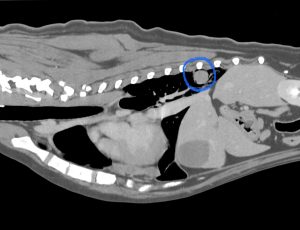

CT検査では、左前葉に7cmのしこりが1つ、右後葉に2cmのしこりが1つ見つかりました。お腹や、頭の方には腫瘍らしき病変はなく、転移性の肺腫瘍は否定的でした。左右の肺にしこりがあり、肺の中で転移している可能性が考えられましたが、その他には肺内転移を疑う病変がないため手術は可能と考えて、飼い主さんと相談の上、両方とも切除することになりました。

肺は全体の50〜60%切除すると術後に呼吸状態が悪くなるため、大きい方は肺を丸ごと切除、小さい方は特殊な器具を用いて部分切除にすることで、肺は70%ほど残せるように計画しました。

手術は左右から肋間開胸を行い、それぞれの腫瘍を無事に取ることができました。